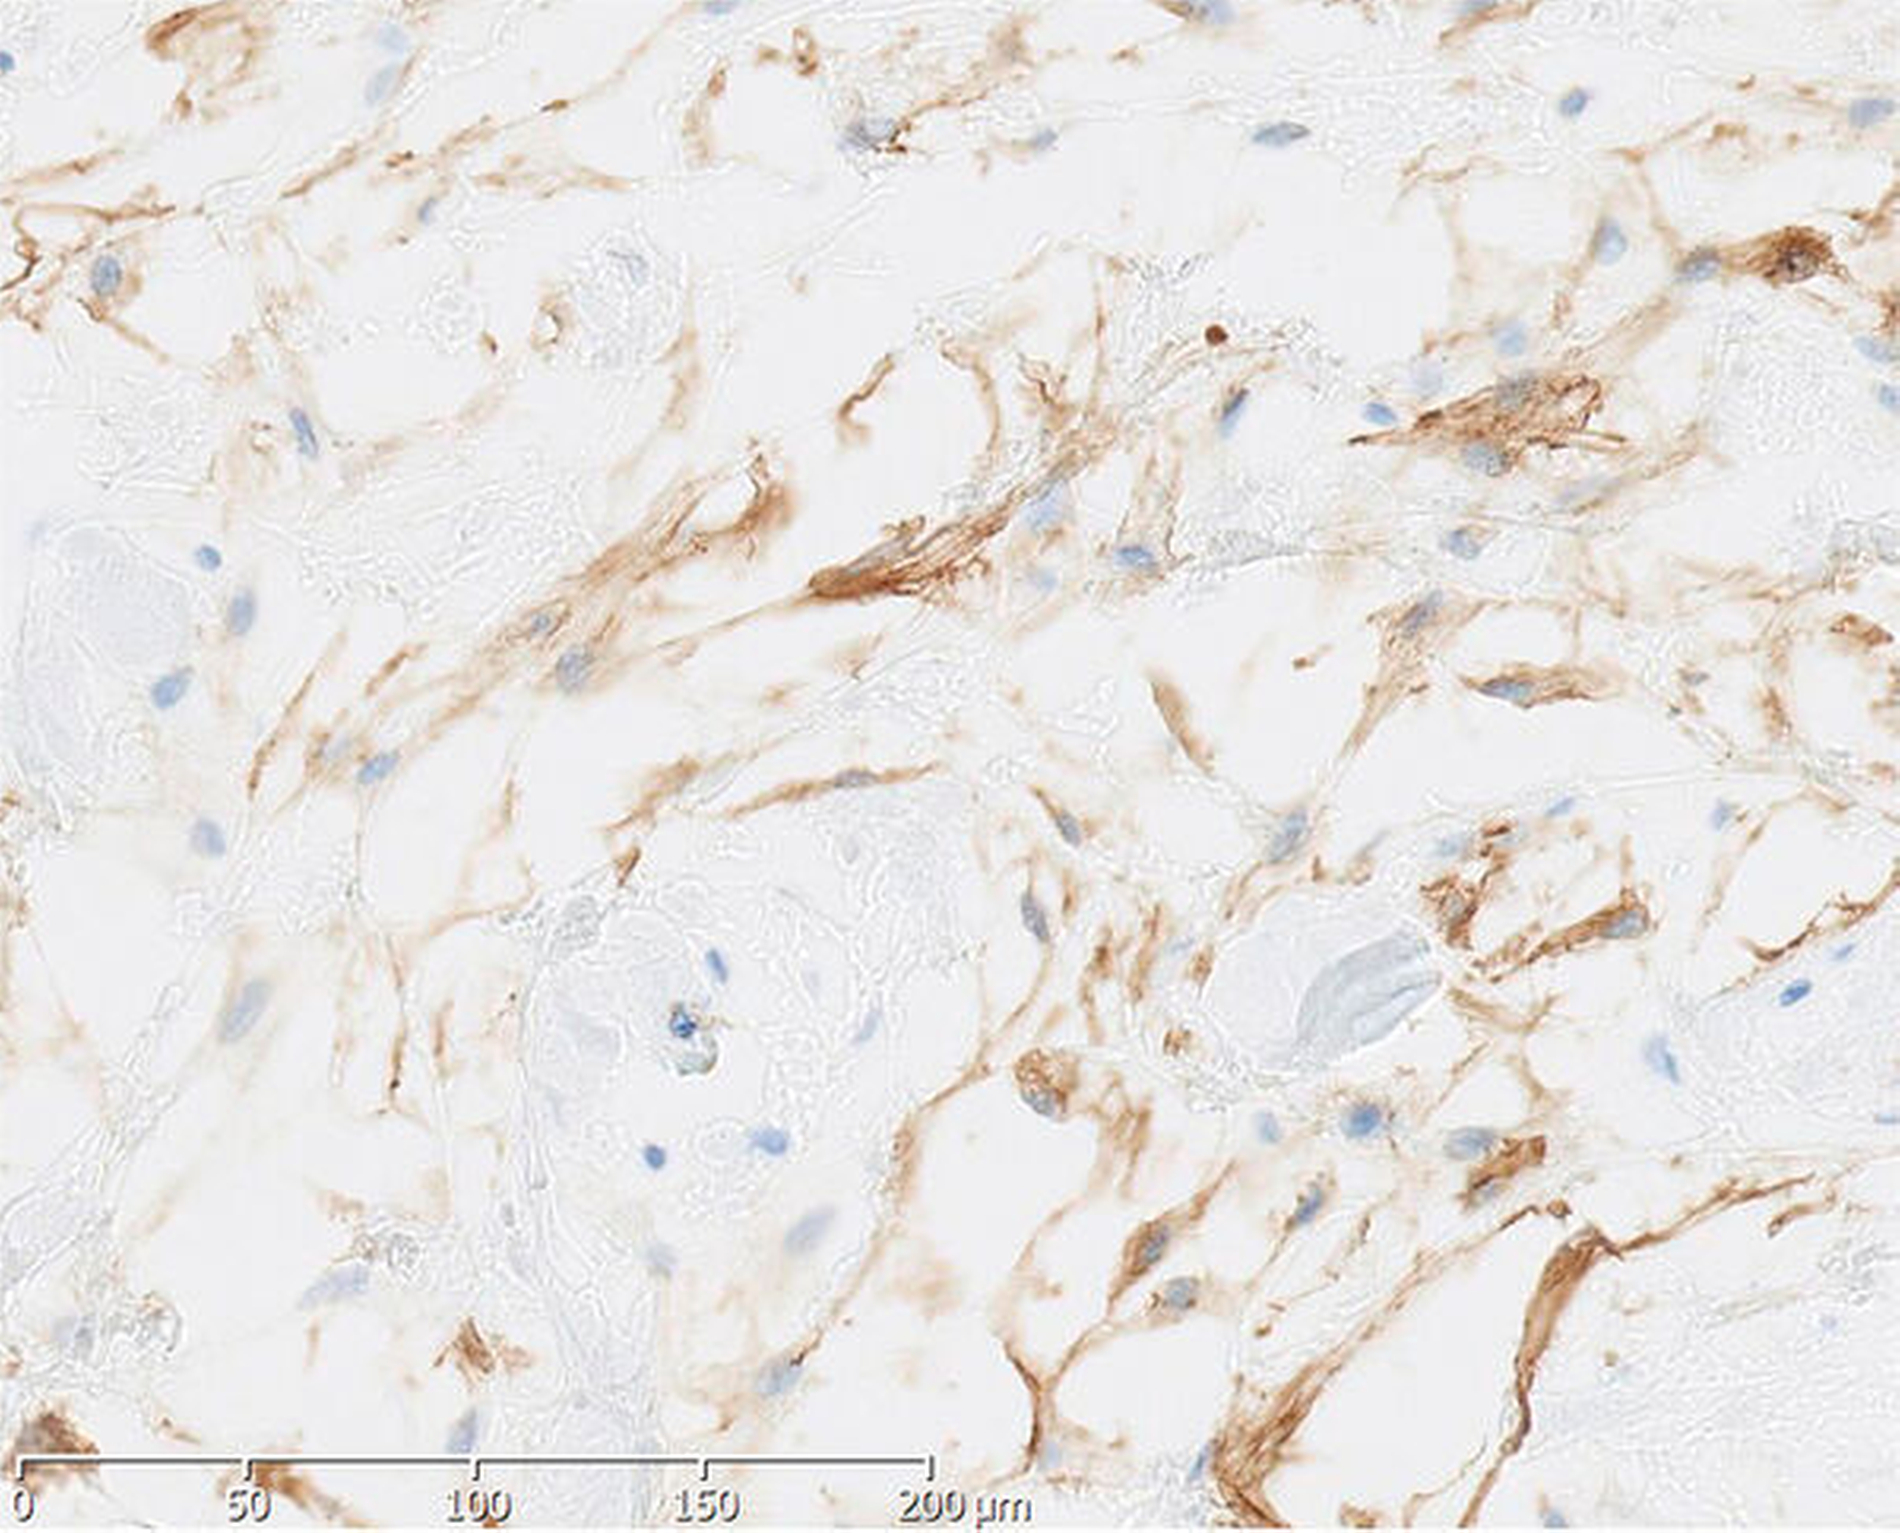

In der histopathologischen Aufbereitung zeigte sich in den weichgewebigen Resektaten eine interstitielle myxoide Matrix mit spindeligen Zellen mit geringen Kerngrößenschwankungen. Zur weiteren Befundeinordnung erfolgte eine immunhistochemische Aufbereitung. Dabei waren Anteile eines Myxofibroms mit fokal chronisch-erosiven Entzündungen im Bereich der Oberfläche sowie eine Hyperplasie des Plattenepithels erkennbar.

Um Aussagen zur intraossären Ausbreitung sowie zur Dignität des nachgewiesenen Myxofibroms treffen zu können, wurde das Material weiter aufbereitet. In der Alcian-PAS-Färbung zeigten sich keine infiltrativen Anteile des beschriebenen Myxofibroms sowie keine Destruktion des Knochengewebes. Es gab keine Anzeichen für Malignität.